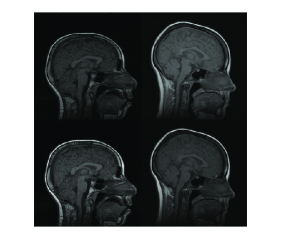

In Figure 9, three example registration results of randomly and nonlinearly warped images are shown. Capturing signal intensity variations during registration process with intensity standardization method leads to assesment of visual comparision of registered source and target images with warping grid. Evaluation of the registration results is summarized in Table-2. The table shows that large and small scale deformations are captured accurately on the standard intensity scale. Resulting images have fixed intensity meanings even there is large intensity variations initially.

Figure 9: Resulting registration of images with random nonlinear warps. Each row includes source, target, registered source and estimated warping grid

Refer to caption